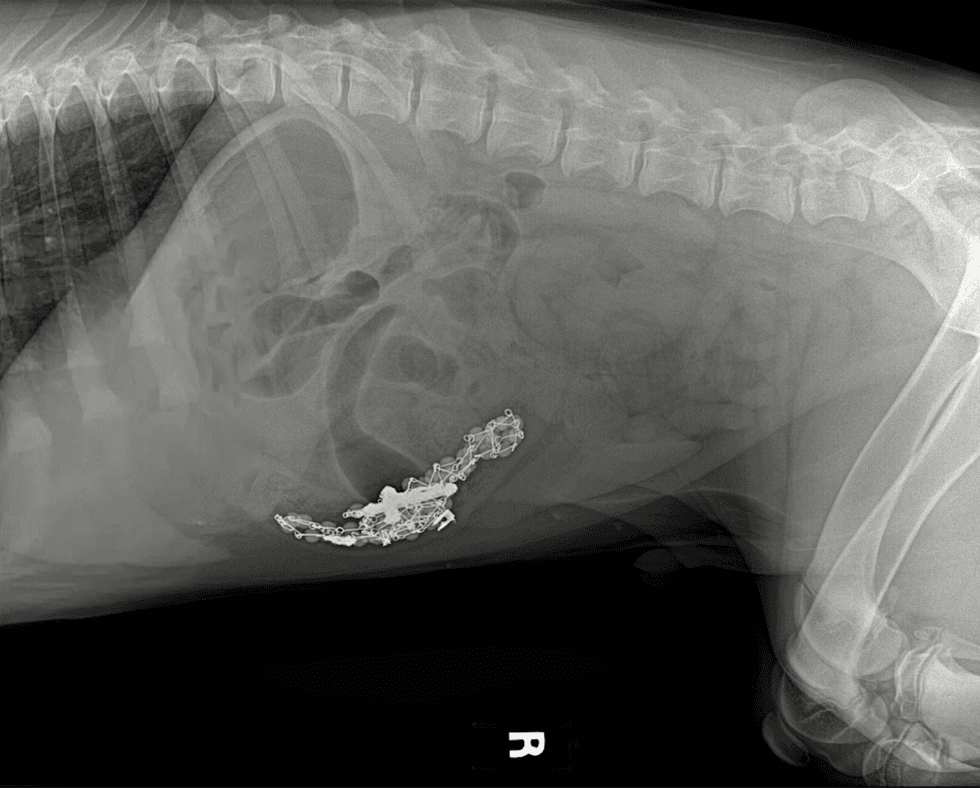

Gladwyne Animal Hospital in Pennsylvania posted an X-Ray image of a pup who swallowed rosary beads. In the scan, posted on Facebook, you can clearly see the outline of the beads in the puppy's belly.

Thankfully, the post also revealed that the puppy is doing just fine now as he awaits his miracle.